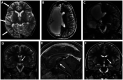

Figures